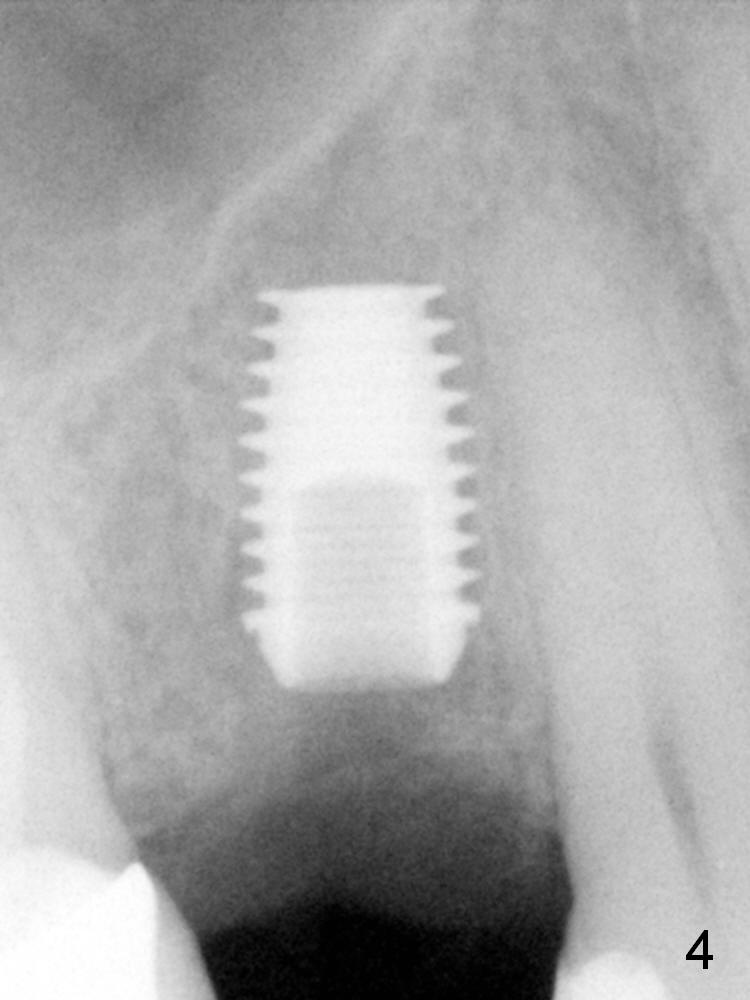

ZC is a 36-year-old man without significant medical history. His chief complaint is "I have Pain sometimes". His oral hygiene is poor (Fig.1). The tooth #3 has large MO caries with periapical radiolucency (*). The tooth #4 is non-salvageable (Fig.1,2). Four months after scaling & root planing, RCT and crown for #3 and extraction of #4 (Fig.3), a 5x8 mm Bicon implant is placed at the site of #4 (Fig.4). Peri-implant space is obliterated 5 months postop (Fig.5). The 2nd surgery is performed to uncover the implant and to place a temporary abutment. Two weeks later, a 5.0x.3.0 mm 0 degree Stealth Abutment 3.0 mm Post is placed (Fig.6). The most recent recall PA shows no bone loss for 5 years 3 months post cementation (Fig.7).